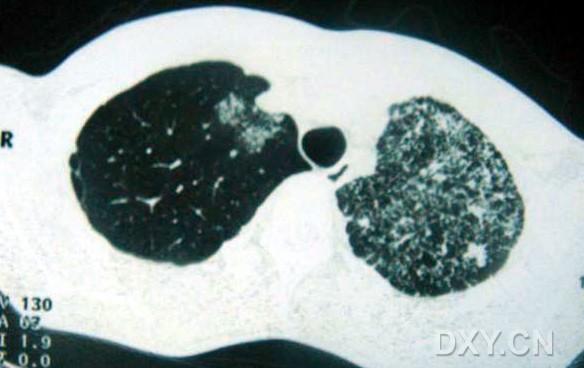

影像表現(xiàn):

兩肺彌漫性顆粒狀陰影,部分陰影融合呈團塊狀,可見支氣管氣相;

呈非對稱,非均勻分布性,部分肺野呈磨玻璃密度;

多處胸膜局限性增厚,胸水征(--)縱隔窗為正常。

臨床表現(xiàn)提示為非細菌性感染性疾病,ct表現(xiàn)為以肺泡實變?yōu)橹鞯膹浡躁幱埃?/font>

病理結(jié)果為:過敏性肺泡炎。